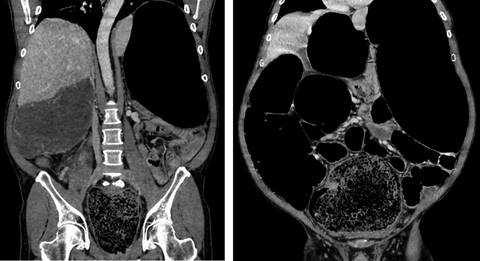

En la primera gasometría resulta llamativa la escasa afectación del equilibrio ácido-base (pH 7.4, PCO2 40.4 mmHg, CO3H- 28.3 mEq/L) e iónico (K+ 3.4, Na++ 135, Ca++ 1.10, Cl- 97), aunque presenta hemoglobina 16.4 g/dL y lactato 3.8 mmol/L. La analítica muestra 520,000 plaquetas/µL, sin afectación renal (urea 51 mg/dL, creatinina 1.16 mg/dL) ni trastornos de la coagulación (INR [International Normalized Ratio] 1.16, TTPAratio [Tiempo De Tromboplastina Parcial Activado-Relación] 1.11). La tomografía axial computarizada (TAC) muestra un gran fecaloma en ampolla rectal que provoca dilatación significativa colorrectal (16 cm en colon transverso y 13 cm en ciego) de íleon y yeyuno distal (Figuras 2 y 3). El estómago e intestino delgado proximal están colapsados y no existe neumoperitoneo ni líquido libre intraabdominal.